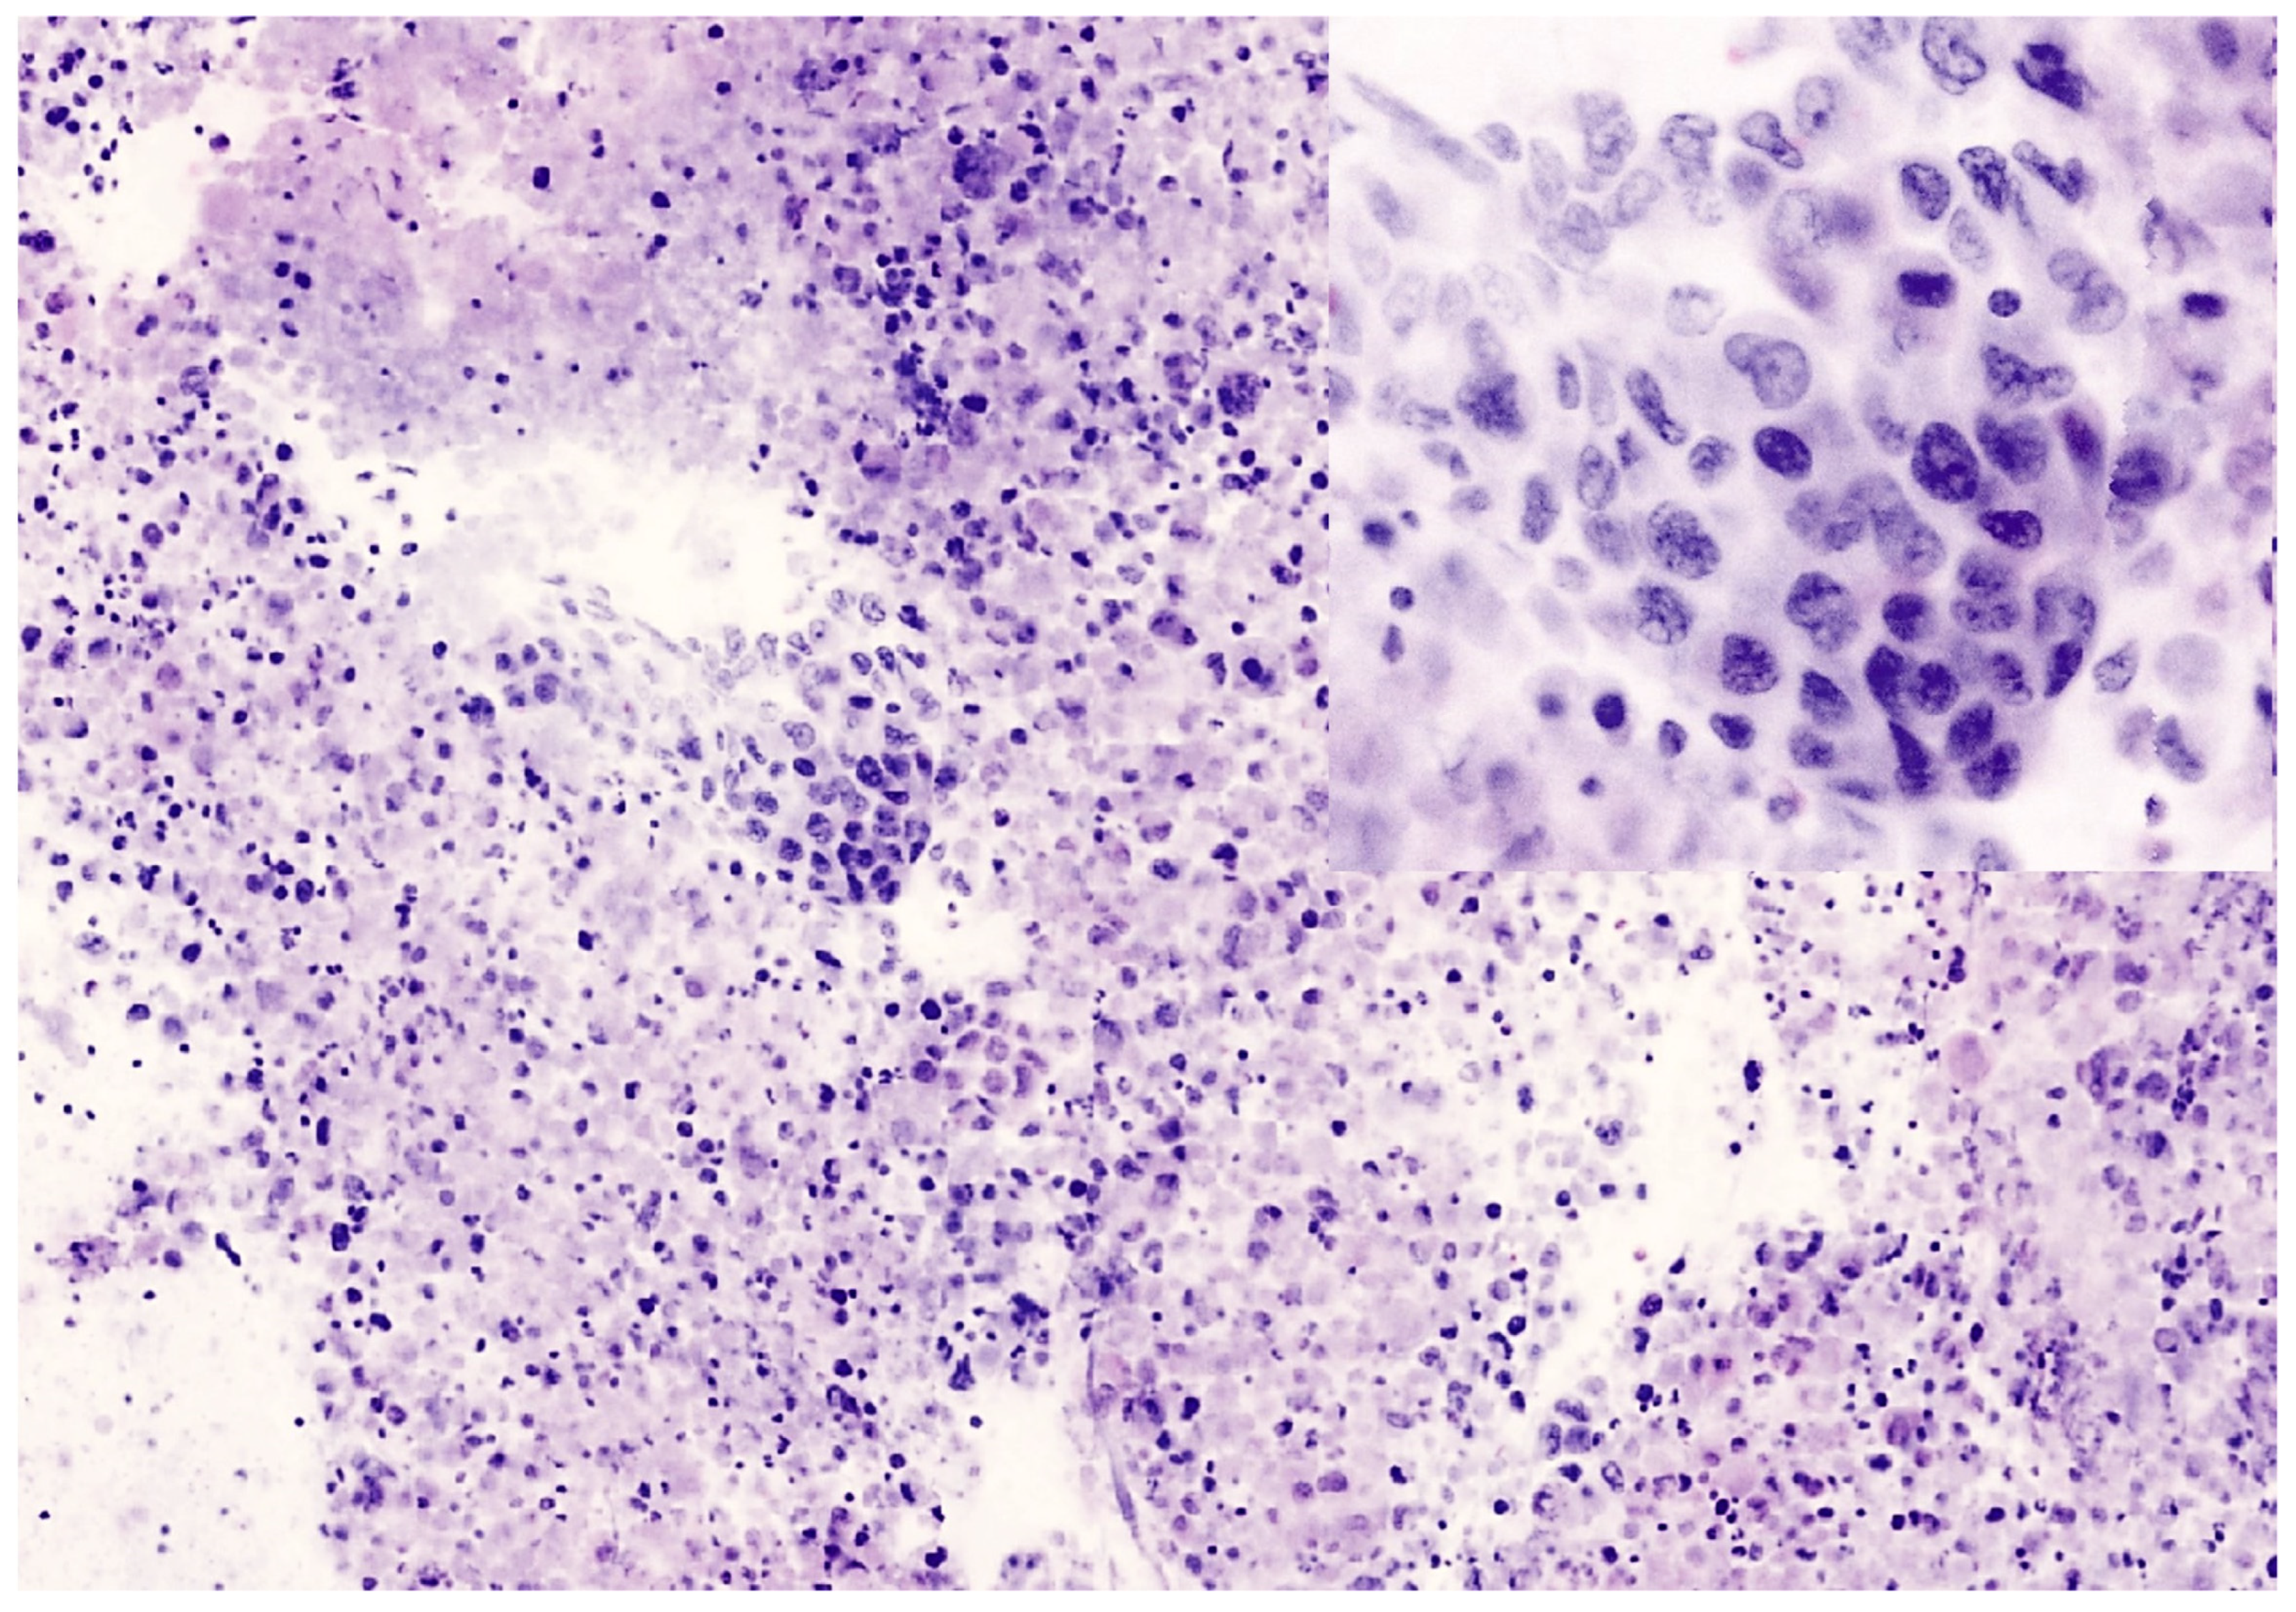

Figure 2. Metastasis of lung adenocarcinoma in a mediastinal node. (a) FCM image show malignant cells with irregular nuclei, evident nucleoli and faint stained cytoplasm, arranged in solid group with pseudo-acinar features. Intense neutrophilic inflammatory background is evident. (b) Permanent paraffin section from the same case. Malignant cells are arranged in cluster with pseudo-acinar growth. The bloody and inflammatory background is more evident.